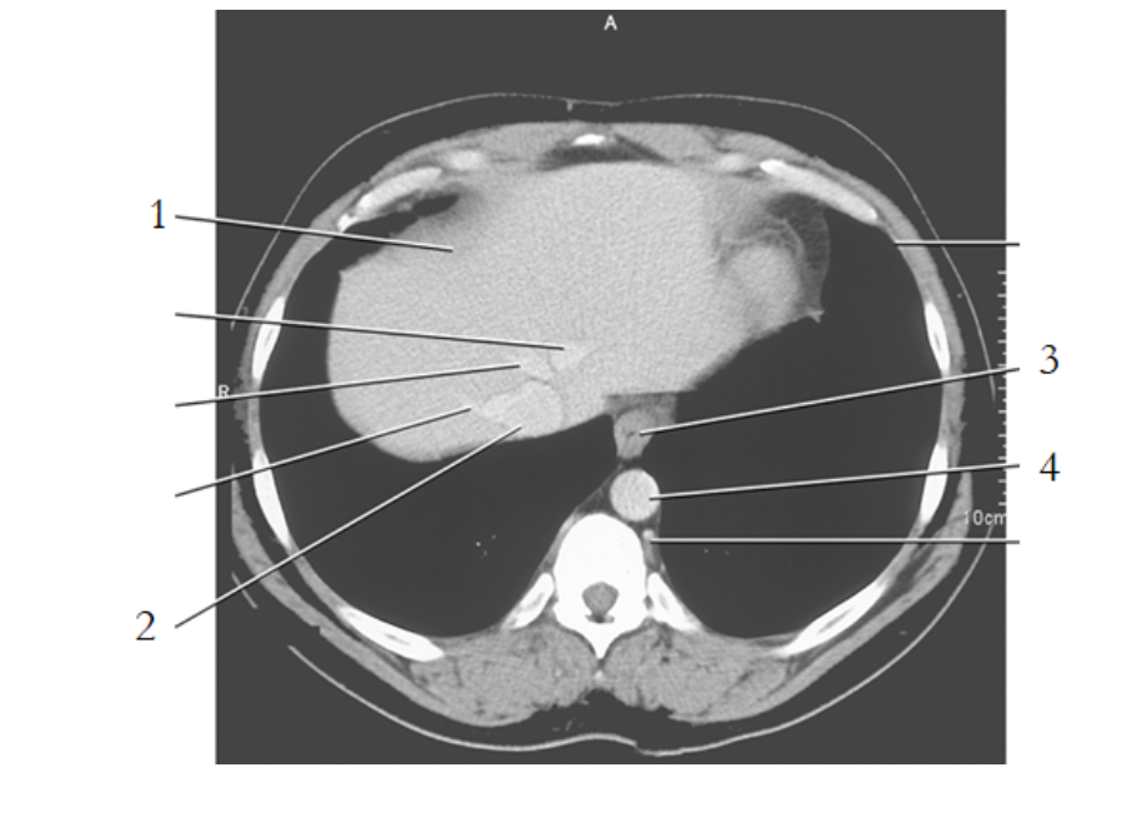

1

liver

3

esophagus

9

crus of diaphragm

8

IVC

14

gallbladder